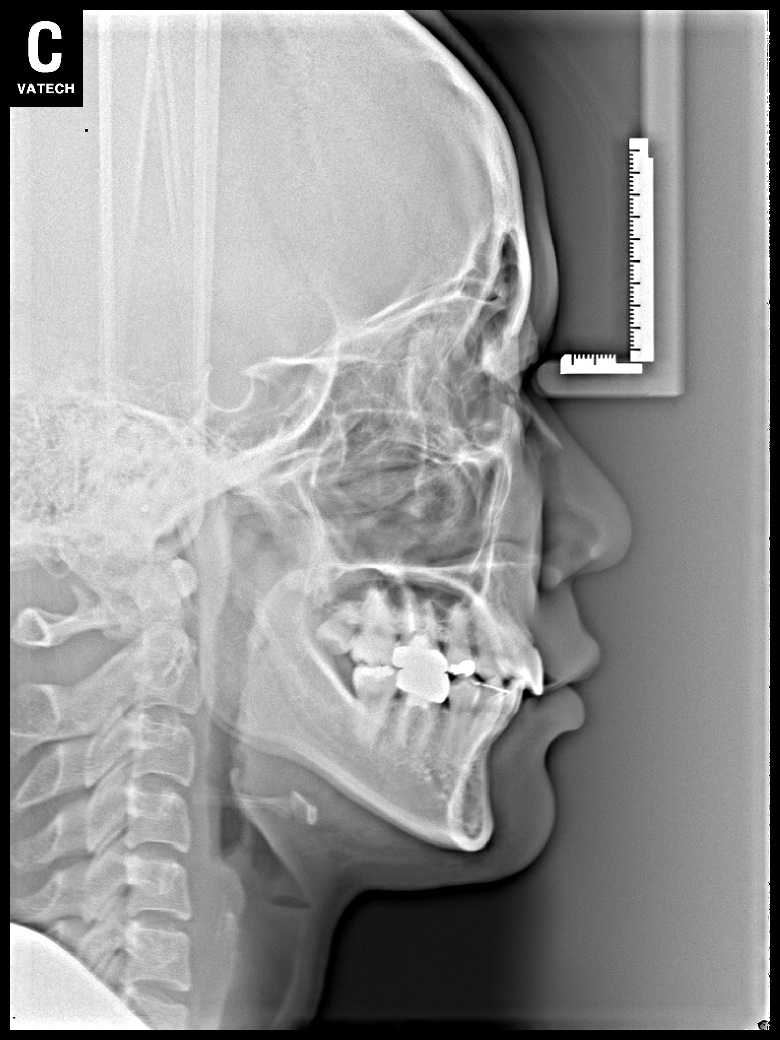

치료 전 사진입니다.